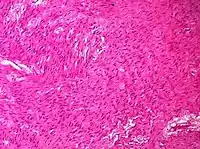

Sex cord-stromal tumorOvarian fibroma 1.5%0%Spindle-shaped fibroblastic cells and abundant collagen.[8]